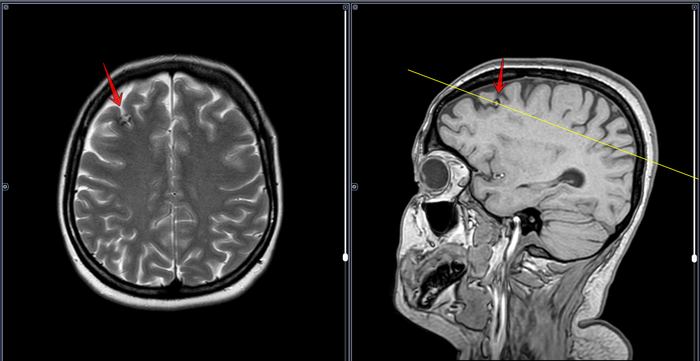

Анамнез: возрастная пациентка, жалобы на частые головные боли, особенно в области затылка. Падала в ванной на плитку, ударилась задней частью головы 7 мес. назад.

МР-картина хронических субдуральных гематом обоих полушарий головного мозга(более крупная слева). МР- признаки очаговых изменений головного мозга, сосудистого генеза ( микроангиопатия, Fazekas 3). Диффузная церебральная атрофия 1 ст. ( по шкале GCA).

Категория годности при наличии аналогичных гематом у призывника, будет по ст.25(Травмы головного и спинного мозга и их последствия. Последствия поражений центральной нервной системы от воздействия внешних факторов:)- Статья предусматривает наличие изменений центральной нервной системы и нарушение ее функций вследствие перенесенной травмы головного или спинного мозга, осложнений вследствие травматических повреждений центральной нервной системы, а также воздействия воздушной взрывной волны и других внешних факторов, итоговая категория годности будет зависть от наличия и степени выраженности неврологических нарушений.